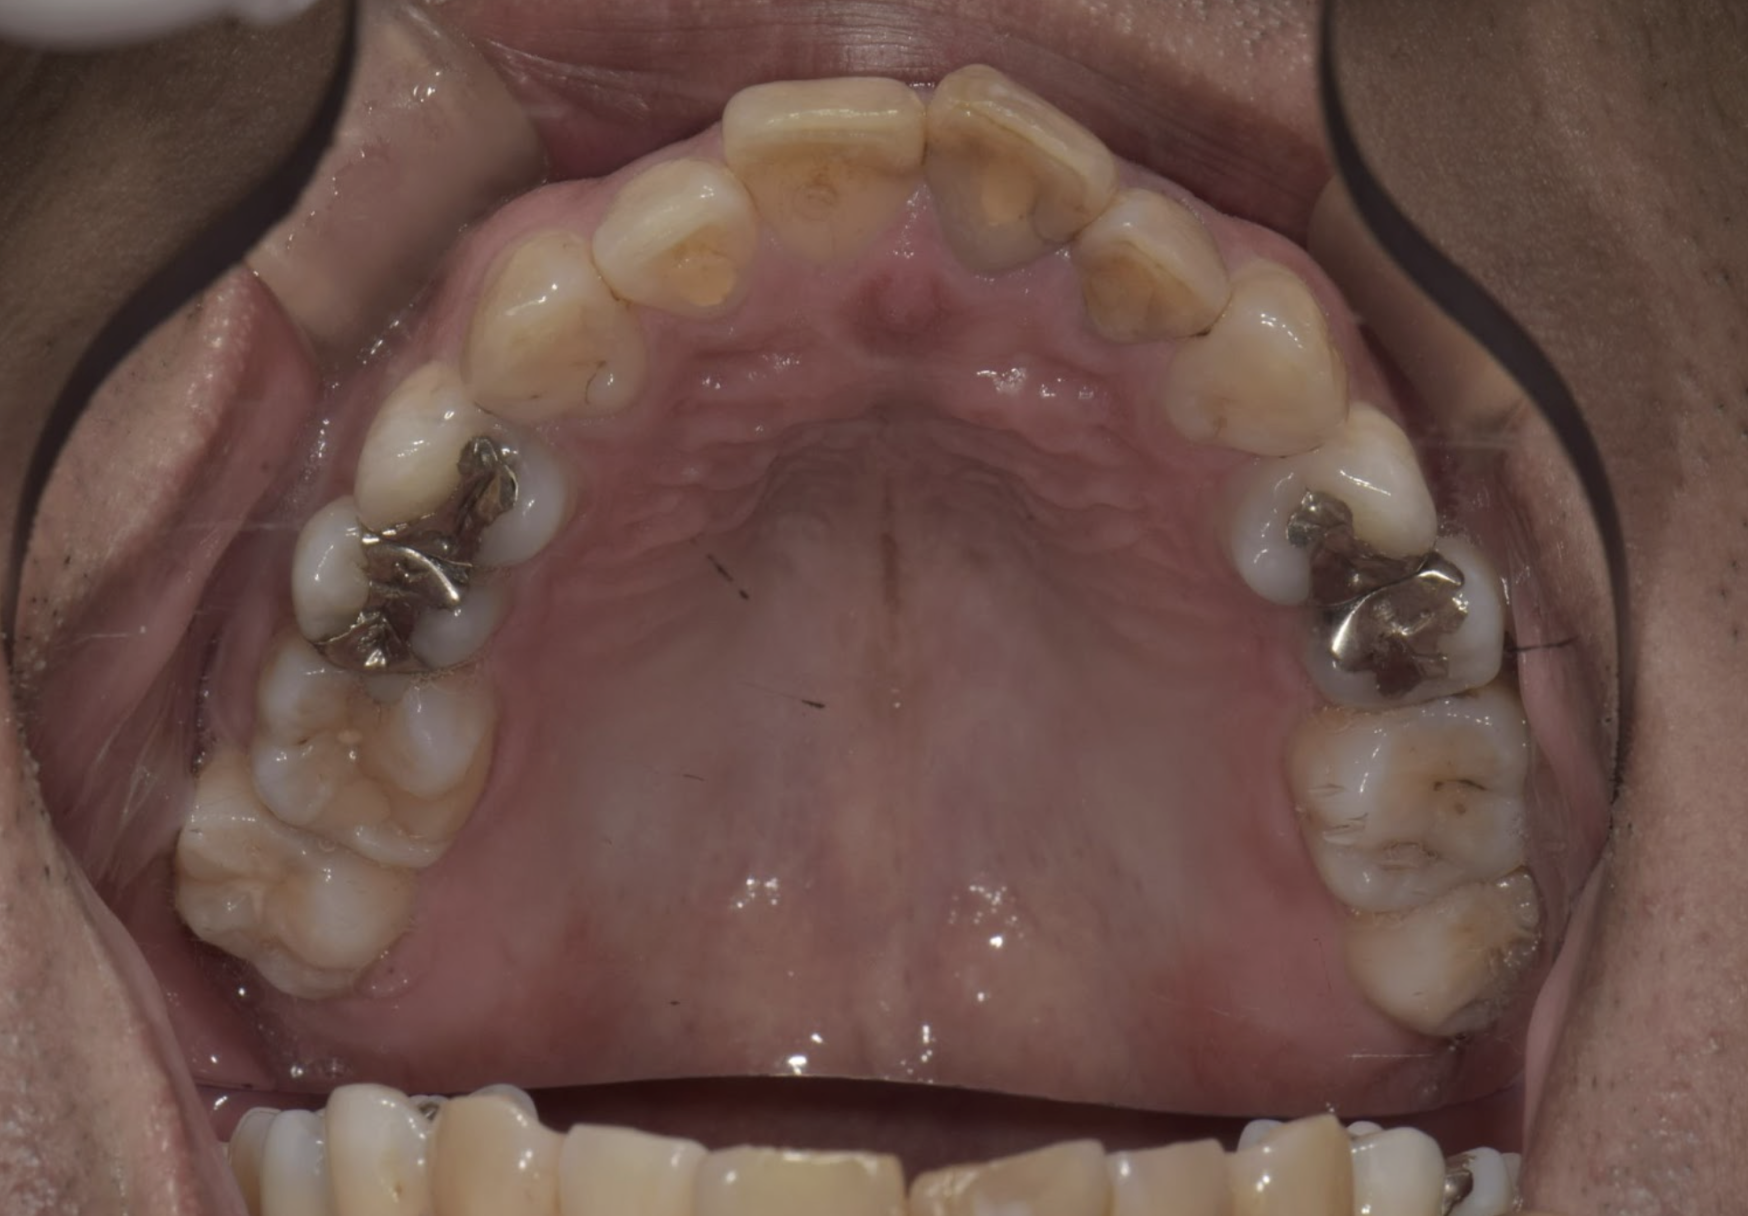

治療の症例

2025/04/22 セレック

OS1457様

通院時年齢 41歳

性別 男性

通院目的 虫歯が気になる

診断 左上45う蝕

処置内容 (または主訴) セレックインレー

通院期間 3回(2か月)

費用

セレックインレー 77,000円×2

リスク・副作用

研磨や調整が難しく定期的なメンテナンスが必要になることがある、自由診療となるため費用が高額となる ジルコニアに比べ天然歯に近い分、破折のリスクがある かみ合わせの変化により適宜調整を必要とする 知覚過敏の出現の可能性がある